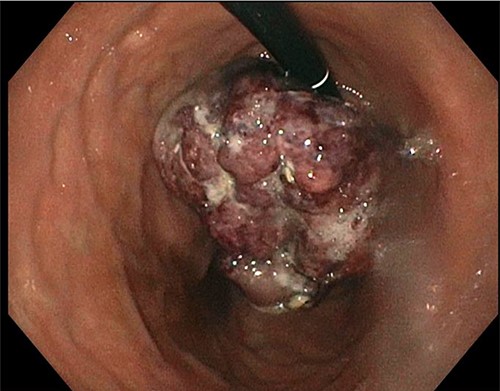

A 77-year-old male was seen in the general surgery clinic in November 2021 for significant gastrointestinal bleeding secondary to metastatic renal cell cancer to the stomach. He was scheduled for a total gastrectomy at that time. His pertinent history consisted of reoccurring blood transfusions from gastric bleed anemia for months most recently requiring a transfusion of one-unit packed RBCs (pRBC) per week. Past medical history was significant for chronic kidney disease stage 3A, hypertension, type 2 diabetes mellitus, hyperlipidemia and stage 4 left kidney clear cell carcinoma with metastases to the diaphragm and stomach. He underwent a left nephrectomy with chemotherapy treatment in April 2016 and open resection of a metastatic lesion to the diaphragm in January 2019. An esophagogastroduodenoscopy (EGD) done in October 2021 showed an 8 cm large, friable, ulcerated mass at the gastric cardia taking up most of the fundus (Fig. 1). Biopsies of the mass demonstrated clear-cell carcinoma compatible with metastatic RCC.